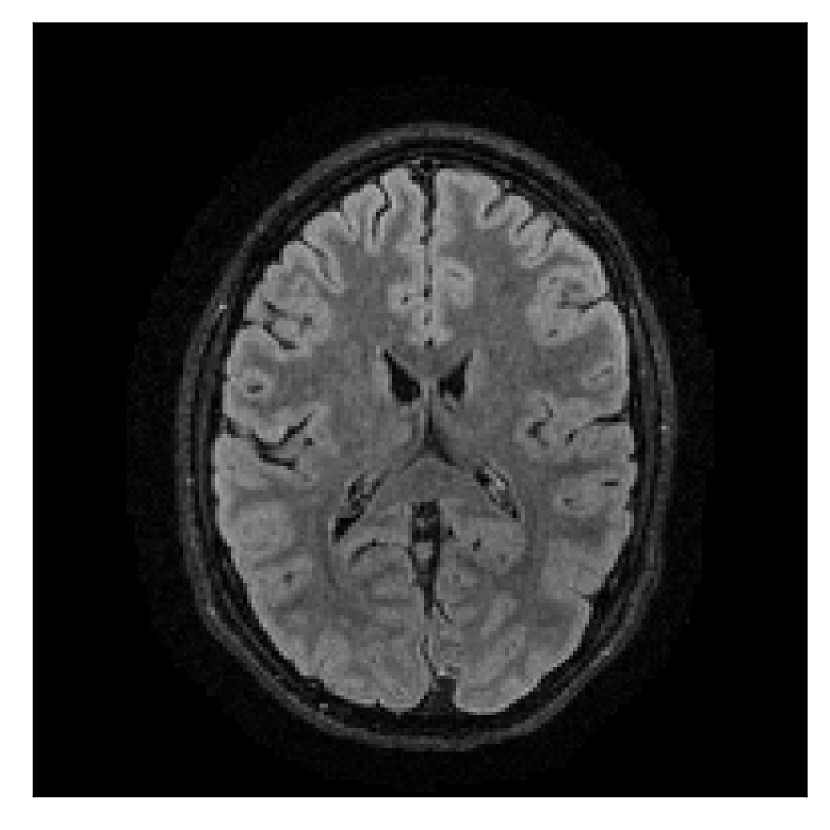

We consider three levels of motion corruption: (i) the volunteer moves once, (ii) the volunteer moves twice, and (iii) the volunteer moves five times. The volunteer is instructed to change its head position every time it is prompted to do so, and maintain that position in between instructions. We use T2-FLAIR-weighted contrasts as corrupted scans, with T1-weighted contrast as a reference (see Table 1 for further details). The corrupted acquisition employs randomized sampling.

4.1 Experiment 1: robustness test

We gather the results for the robustness test described in Section 3.1 (volunteer 1) in Figures 2, 4, and 6 for motion corruption mechanisms associated to one, two, and five changes of position, respectively. Furthermore, we juxtapose the corrected images with varying degrees of corruption in Figure 8. We observe that the proposed method consistently ameliorates the corrupted scan. The quality indexes based on PSNR and SSIM show only a modest decrease in correction quality as a function of motion complexity (Figure 8).

| Section 3.1, Figure 2 | Sagittal | 23.94 | 27.95 | 0.7068 | 0.7936 |

| Coronal | 26.66 | 29.82 | 0.7653 | 0.8332 | |

| Axial | 25.40 | 30.16 | 0.7616 | 0.8490 | |

| Section 3.1, Figure 2 | T2-FLAIR | Completely corrected | Some blurring | No additional artifacts | Good grey white matter differentiation |